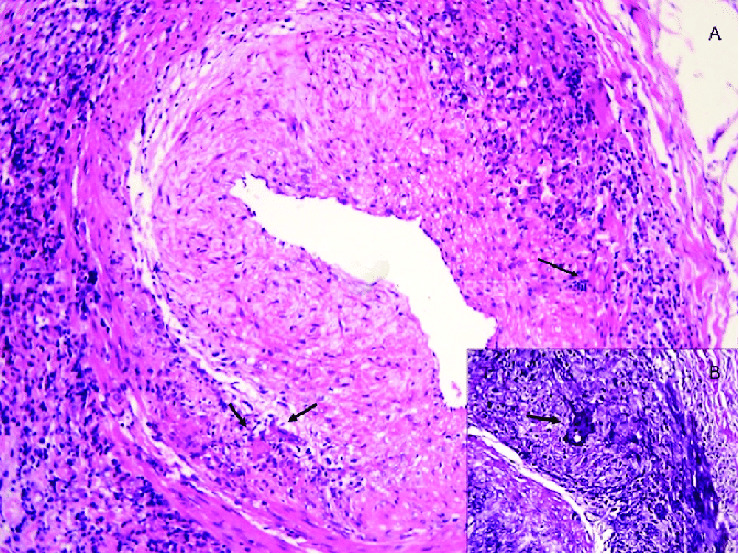

巨细胞动脉炎(GCA),也称为颞动脉炎,是50岁以上人群中最常见的全身性血管炎,由于其非特异性症状,如发烧、头痛和疲劳,给诊断带来了挑战。本病例报告描述了一位70多岁男性患者的细节,他表现为复发性间歇性发热,原因不明,经过广泛的检查后最终被诊断为GCA。他最初的CT扫描和实验室检查结果并不显著。然而,在风湿病检查显示红细胞沉降率(ESR)和c反应蛋白(CRP)水平升高,并伴有共济失调和头痛的新症状后,进行了颞动脉活检(TAB)并确认患者患有GCA。本病例强调了诊断GCA的困难,主要是由于医生的锚定偏差,特别是在没有典型症状的情况下。该病例还表明,需要提高认识并及时评估潜在的GCA症状,以预防严重并发症。公共教育以及改进医院规程可导致更早发现和治疗GCA,降低发病风险。

Giant cell arteritis (GCA), also known as temporal arteritis, is the most common systemic vasculitis in individuals over 50 and presents diagnostic challenges due to its nonspecific symptoms such as fever, headache, and fatigue. This case report describes the details of a male patient in his 70s who presented with recurrent intermittent fevers of unknown origin and was ultimately diagnosed with GCA after an extensive workup. His initial CT scans and lab tests were unremarkable. However, after a rheumatological workup displayed elevated erythrocyte sedimentation rate (ESR) and C-reactive protein (CRP) levels, along with new symptoms of ataxia and headaches, a temporal artery biopsy (TAB) was performed and confirmed the patient had GCA. This case underscores the difficulty in diagnosing GCA primarily due to physician anchoring bias, particularly when typical symptoms are not present. The case also showcases the need for increased awareness and prompt evaluation of potential GCA symptoms to prevent severe complications. Public education as well as improved hospital protocols can lead to earlier detection and treatment of GCA, reducing the risk of morbidity.